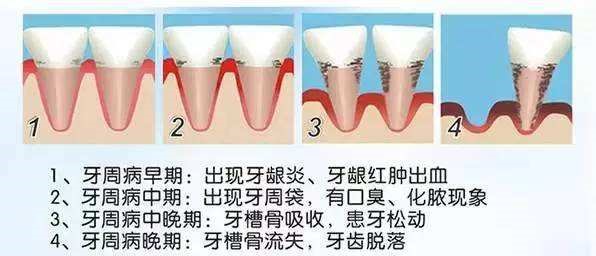

牙周病最常见的症状是牙龈出血,口腔异味,晚期可出现牙齿松动、移位。

1.牙龈炎:牙周病早期表现,表现为牙龈红肿、刷牙出血。及时治疗,此阶段可痊愈。如果不及时治疗,炎症会进一步发展,引起深部的牙槽骨吸收,发展成牙周炎。

2.轻度的牙周炎:可见牙龈红肿、刷牙出血、口臭;患者常常因为不会疼痛而加以忽略。

3.中度牙周炎:出现咀嚼无力、口臭、牙龈退缩、牙根暴露、出现牙缝、牙床肿痛;因为牙龈的肿痛时起时消,患者认为是所谓的上火造成,依然没有引起足够的重视。

4.重度牙周炎:出现牙齿松动、移位、疼痛、溢脓等症状,无法咀嚼食物,最终牙齿脱落。